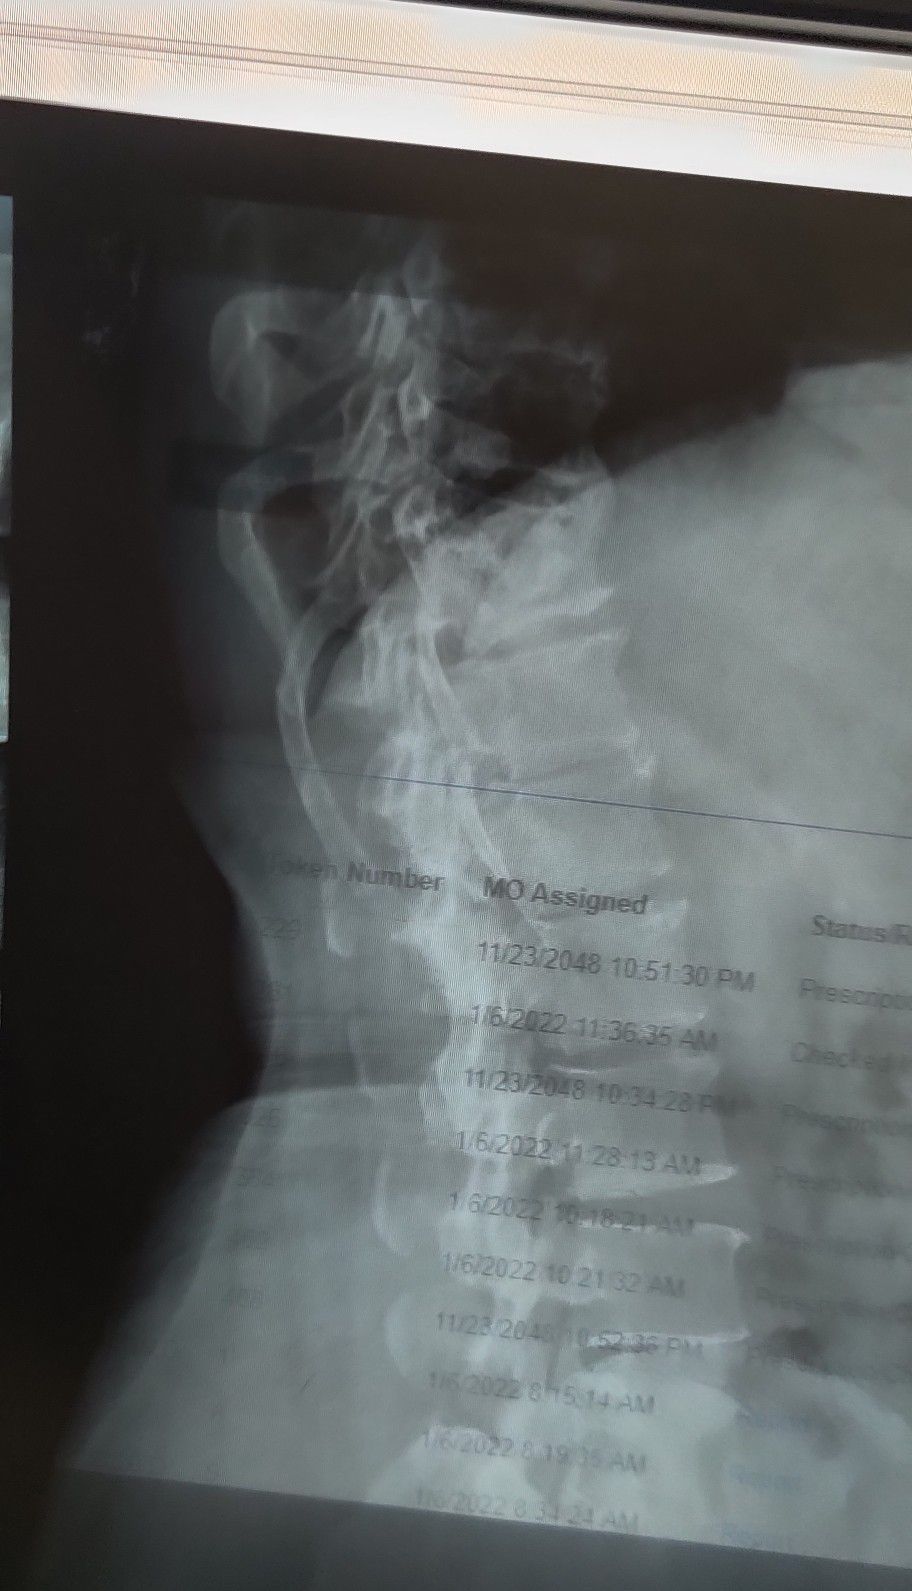

Osteoporosis + Osteophytes + Vertebral Fracture

Ortho

Vertebrae

Osteoporosis

Few causes of osteoporosis are: Smoking Binge drinking Gastrointestinal disease Hyperthyroidism Autoimmune disease Coeliac disease Cushing's syndrome Hyperparathyroidism Low body weight

Management of osteoporosis: If you have osteoporosis, medical treatment can prevent further bone loss and reduce your risk of bone fractures. Treatment options for osteoporosis include dietary changes, exercise, lifestyle changes, falls prevention, supplements and medications.